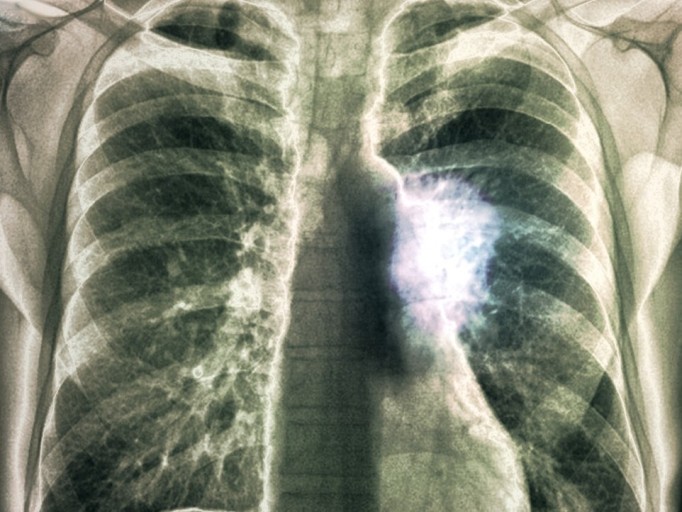

폐암 증상에는 기침, 체중 감소 흉통, 혈담 즉 피가 섞인 가래, 호흡곤란 등이 있지만, 위 증상은 다른 폐 질환에서도 나타날 수 있는 증상으로 구분하기가 어렵다. 그리고 폐암 초기에는 특별한 증상이 없는 경우가 대부분이라서 최근 흡연뿐 아니라 미세먼지 등 여러가지 요인으로 폐암이 발생하는 경우가 많아 정기검진으로 조기에 발견하는 것이 중요며 폐암 검진을 위해서는 특히나 저선량 흉부 CT를 촬영하는 것이 좋다라고 전문가들은 말하고 있습니다..

보통 숨소리는 크게 들리지 않지만, 목이나 폐 부분에 뭐가 걸린 느낌이 나듯이 숨소리가 거칠어지는 걸 느낍니다.면 폐에 문제가 생겼을 확률이 높다. 꼭 내원해 엑스레이를 촬영해 보는 게 바람직합니다..